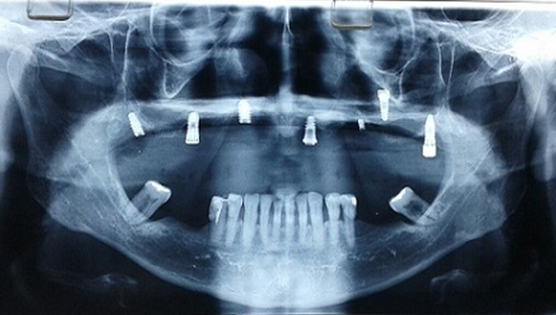

Paciente de 54 anos, do sexo masculino, apresentando boa saúde geral, relatou que procurou atendimento odontológico para realizar a manutenção regular de sua prótese maxilar implanto-suportada do tipo protocolo, instalada há oito anos. O profissional que o atendeu não solicitou nenhum tipo de exame radiográfico e, ao tentar remover a prótese do paciente, não conseguiu remover os parafusos de fixação. Nesse processo, notou a presença de secreção purulenta, então utilizou o fórceps para remoção forçada da prótese, o que terminou por fragmentar dois implantes do paciente de difícil remoção, e fraturar um parafuso de fixação. Um dos implantes foi avulsionado (Figura 1). Perante essa situação, o profissional o informou que seus implantes eram irreparáveis.

O paciente então, procurou o consultório para uma nova avaliação. Foi realizado exame clínico inicial e análise de exames radiográficos (Raio X panorâmico e tomografia computadorizada). Durante a avaliação clínica, houve extravasamento de secreção purulenta de cor amarelo citrino, e, através dos exames radiográficos pode-se constatar que um dos implantes havia rompido a parede do seio maxilar, e ali se instalado, desencadeando a infecção (Figura 2). Através dos exames radiográficos constatou-se também ausência de quantidade óssea suficiente para reabilitação do paciente por meio de novos implantes convencionais, exclusivamente (Figura 3). Além disso, verificou-se que o paciente possuía periodontite nos dentes remanescentes da mandíbula, com mobilidade de grau 3.